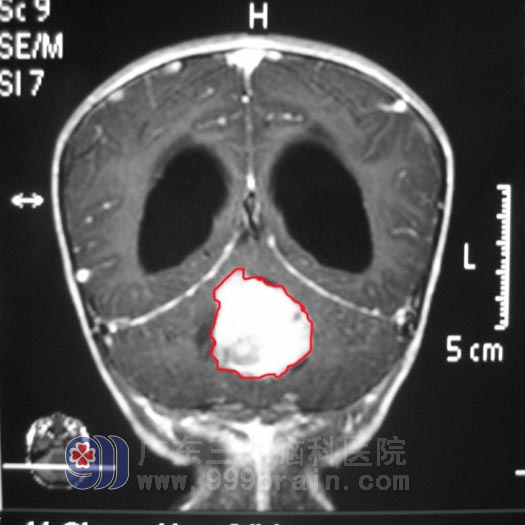

为了给儿子找到最好的医院治疗,小瀚的父亲四处打听,咨询亲朋好友、上网搜索、四处打电话咨询……最终,他选定了广东三九脑科医院。11月29日,小瀚在父母的陪同下来到广东三九脑科医院求医,并找到了神经外五科 鲁明 主任。入院后,鲁明 主任详细了解了小瀚的病情,结合其头颅检查,凭借多年的脑肿瘤诊疗经验,初步诊断为:四脑室占位性病变,梗阻性脑积水。鲁明 主任指出:凭其影像学表现上看,长在小瀚脑子里的肿瘤可能恶性程度较高。12月1日,小瀚在全麻下接受了“右侧脑室腹腔分流术+四脑室内占位切除术”。术程顺利,术后,小瀚头痛呕吐症状消失了,四肢肌力也逐步恢复到正常。术后病理报告示:髓母细胞瘤WHO IV级。术后,小瀚在广东三九脑科医院肿瘤综合治疗中心接受了放化疗,目前已经康复回家。http://www.999brain.com

术前(红色标记为肿瘤)